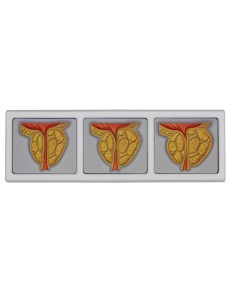

Pelvis masculin 3B Scientifique avec ligaments, vaisseaux, nerfs, plancher pelvien et...